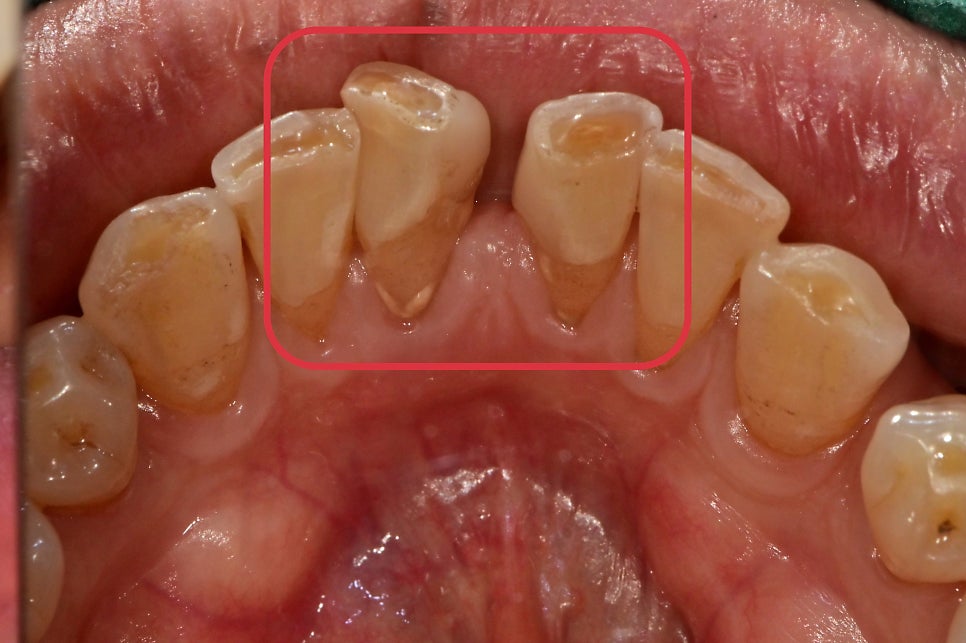

2개의 치아가 치주염으로 인한 치조골 소실로

치아 이동이 일어나 공간이 벌어져있었습니다.

2개의 치아 중 한 개는 치주염이 상당히 많이 진행되어 있었고, 그 옆 치아도 2도 이상의 동요도가 관찰되어 2개의 치아가 발치가 필요했습니다.

2개 치아 위치 모두 임플란트 수술이 가능했지만

아래 앞니라는 것을 고려하여

임플란트 2개를 심는 것보다는 1개만 식립하여

옆에 인공치를 연결하여 치료를 마무리하도록 했습니다